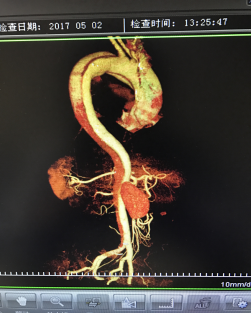

5月2號劉大伯照常早起干活,突然胸部劇烈疼痛,難以忍受,全身大汗,同時伴有右上肢發(fā)涼,他心想這次心絞痛比之前嚴(yán)重的多啊,趕緊叫上孩子到吉林國文醫(yī)院心血管內(nèi)科住院,患者長期高血壓病史,血壓一直控制不理想,大夫給他做了檢查,測左上肢血壓:82/45mmHg,右上肢血壓測不出,心率52次/分,右側(cè)肱動脈、尺動脈、橈動脈搏動消失,左側(cè)股動脈搏動較右側(cè)弱?!霸懔?,雙側(cè)血壓差別這么大,是不是主動脈夾層了?”,接診大夫趕緊找來李主任,李主任反復(fù)詢問患者病情,表情突然凝重起來,患者胸痛這么明顯,血壓低的厲害,主動脈夾層的可能性很大。二話不說,李主任立即聯(lián)系影像科的醫(yī)生準(zhǔn)備做主動脈CTA,移動患者做檢查的過程大夫們非常小心,嚴(yán)密監(jiān)測患者血壓變化情況。兩個小時后結(jié)果出來了,主動脈夾層從升主動脈一直撕裂到左側(cè)髂總動脈!??!

從開始學(xué)醫(yī)到現(xiàn)在已經(jīng)快9年了,主動脈夾層患者也見過一些,但像劉大伯這種危險類型的還是第一次見到,心里真的為他捏把汗,撕裂的主動脈隨時都有可能破裂,生命隨時可能終止,要知道主動脈夾層的死亡率非常的高,約50%的患者發(fā)病后48小時死亡,約90%的患者發(fā)病1個月內(nèi)死亡。